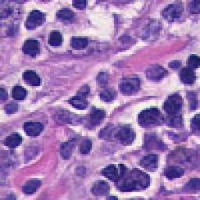

Medical Diagnostics & Research: Researchers and healthcare providers can use LDANN-BASIC to assist in the identification of lymphocyte classes, helping to diagnose diseases like leukemia or lymphoma more efficiently and enhancing our understanding of the immune system.

Pharmaceutical Development & Drug Testing: The model can be employed in pharmaceutical labs to study the effects of new drugs on lymphocyte populations, contributing to the development of more effective medications or therapies targeting specific immune conditions.

Automated Clinical Laboratory Systems: LDANN-BASIC can be integrated into automated image analysis workflows within clinical laboratories, streamlining the process of analyzing patient samples and reducing the risk of human error in lymphocyte classification.

Educational Purposes: The model can serve as a teaching tool for medical students, clinical laboratory scientists, and immunology researchers to learn and visually understand different types of lymphocytes, thereby improving their skills and knowledge in the field of histology and pathology.

Remote and Telemedicine Diagnostics: LDANN-BASIC can be used in remote healthcare settings or telemedical diagnostic systems, enabling healthcare professionals to analyze blood samples from patients even if they are located in rural or remote areas with limited access to specialized labs.